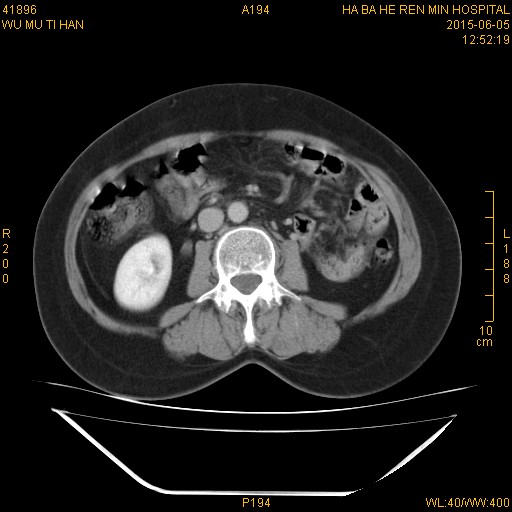

CT50570:膈疝,既往有手术史,具体不详

膈疝,既往有手术史,具体不详

已行手术,左侧膈肌是完整的,是膈膨升

胸腔胃(左侧膈疝)右侧壶腹型肾盂。

左侧膈膨升;左肾动静脉异常交通,动静脉瘘形成;右侧壶腹型肾盂。支持。

倾向:左侧膈膨升;左肾动静脉异常交通,动静脉瘘形成;右侧壶腹型肾盂

1、左侧膈膨升。

2、左肾动静脉异常交通,动静脉瘘形成。

3、右侧肾盂轻度扩张,提示壶腹型肾盂。

1、右侧壶腹型肾盂。

2、胸腔胃。

建议查查右肾积水的原因